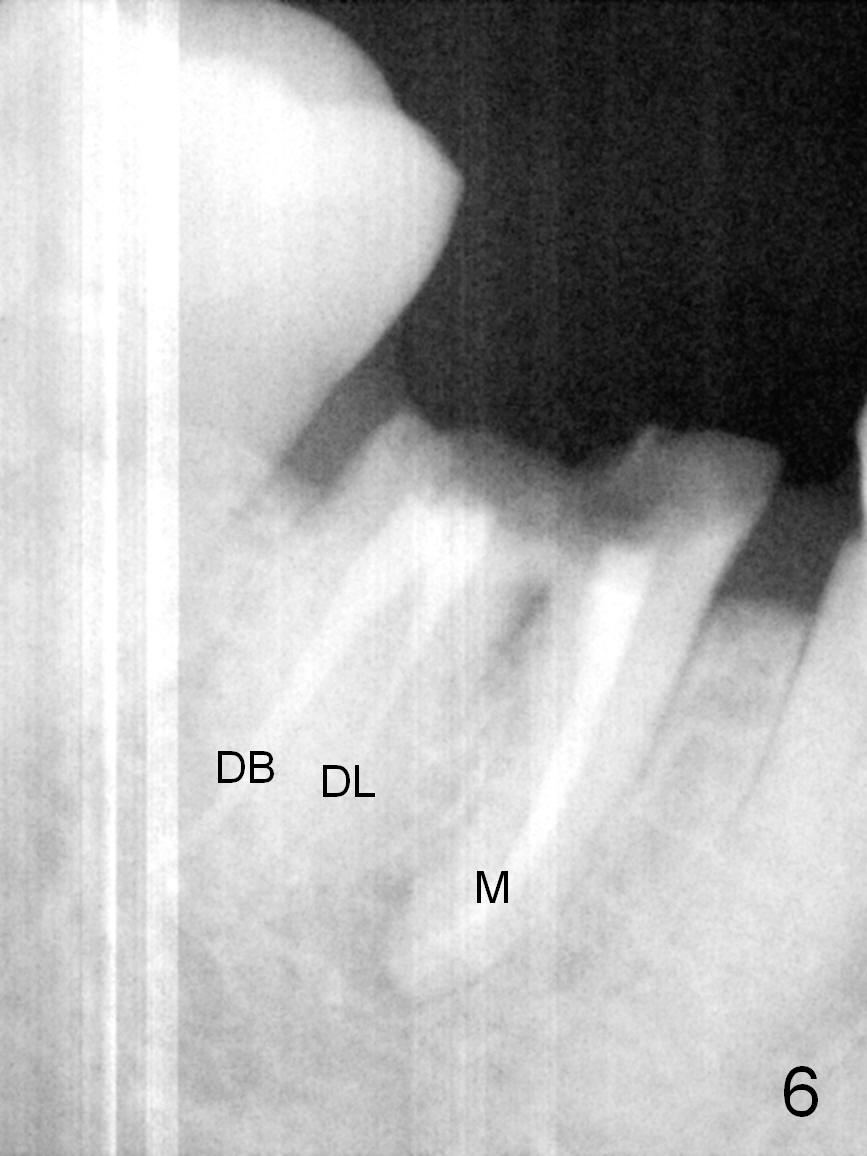

A 68-year-old lady (WQ) had CT taken 3 years ago (Fig.1-3), which show 3 roots (M: mesial; DB: distobuccal; DL: distolingual) of the lower right 1st molar and large caries (C). Recently the tooth fractures after root canal therapy (Fig.4-6).